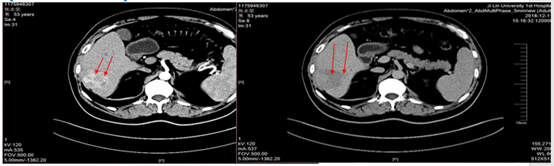

遂予肝动脉化疗栓塞(TACE)治疗,行数字减影血管造影(DSA)可见肝右叶多个结节状肿瘤染色,明确肝左、右动脉分支为肿瘤供血动脉,判定为外科术后复发。

图片

图:第一次TACE治疗

2019年2月21日以碘油5 ml+0.9%氯化钠20 ml+表阿霉素10 mg+雷替曲塞1支稀释后灌注方案行TACE治疗。后复查肝增强CT,未见明显强化,对比2019年1月病灶略缩小,初次TACE治疗达SD。